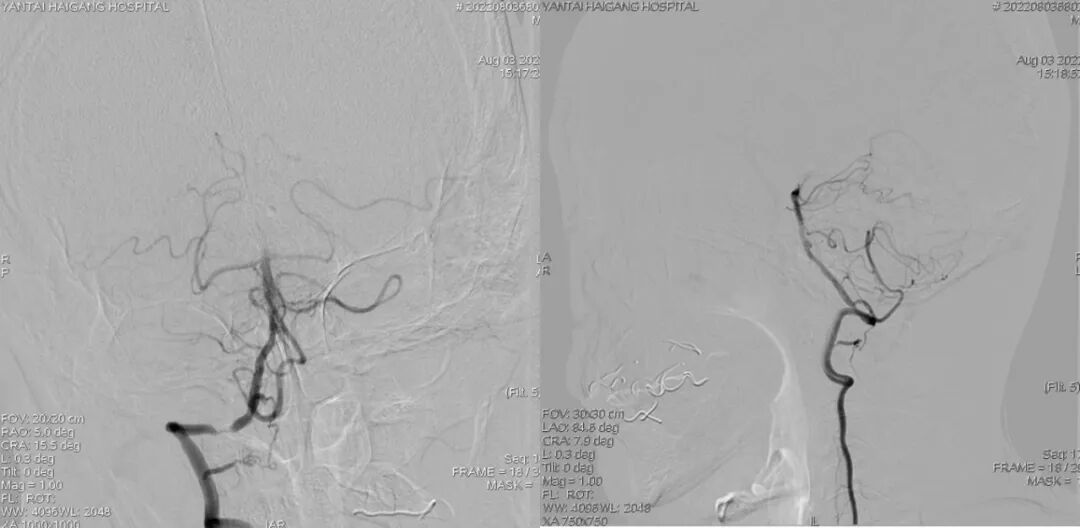

术前造影:

导丝怎么扩【载药时代 球扩天下】NOVA DES®颅内药物洗脱支架在椎动脉颅内段重度狭窄的应用二例_https://www.jmylbn.com_新闻资讯_第18张

左椎动脉+左颈动脉造影:

导丝怎么扩【载药时代 球扩天下】NOVA DES®颅内药物洗脱支架在椎动脉颅内段重度狭窄的应用二例_https://www.jmylbn.com_新闻资讯_第21张

导丝怎么扩【载药时代 球扩天下】NOVA DES®颅内药物洗脱支架在椎动脉颅内段重度狭窄的应用二例_https://www.jmylbn.com_新闻资讯_第22张

导丝怎么扩【载药时代 球扩天下】NOVA DES®颅内药物洗脱支架在椎动脉颅内段重度狭窄的应用二例_https://www.jmylbn.com_新闻资讯_第23张

右椎动脉造影:

导丝怎么扩【载药时代 球扩天下】NOVA DES®颅内药物洗脱支架在椎动脉颅内段重度狭窄的应用二例_https://www.jmylbn.com_新闻资讯_第24张

导丝怎么扩【载药时代 球扩天下】NOVA DES®颅内药物洗脱支架在椎动脉颅内段重度狭窄的应用二例_https://www.jmylbn.com_新闻资讯_第25张

导丝怎么扩【载药时代 球扩天下】NOVA DES®颅内药物洗脱支架在椎动脉颅内段重度狭窄的应用二例_https://www.jmylbn.com_新闻资讯_第26张

右椎动脉动脉正侧位:

导丝怎么扩【载药时代 球扩天下】NOVA DES®颅内药物洗脱支架在椎动脉颅内段重度狭窄的应用二例_https://www.jmylbn.com_新闻资讯_第29张

诊断

主要诊断:

1.右侧椎动脉V4段重度狭窄(90%);

2.高血压病2级 高危;

3.小脑梗死。